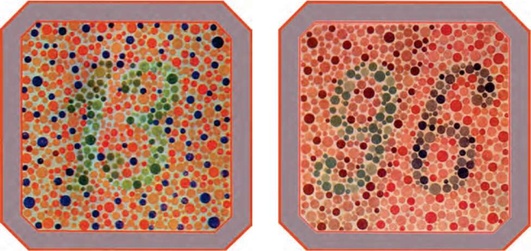

Рис. 8.1. Таблицы Рабкина для проверки цветоощущения